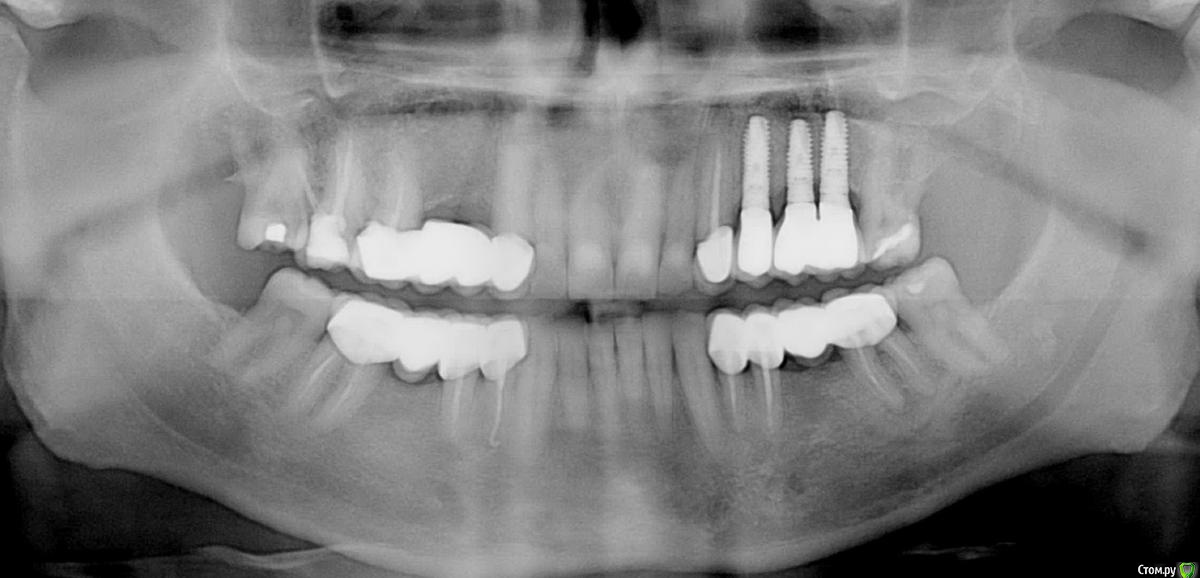

Анестезиолог Опубликовано 27 августа, 2017 Поделиться Опубликовано 27 августа, 2017 Пришло время менять мост на имплантаты (как видите, шестёрка справа сверху никуда, кажется это №16, есть симптоматика периодонтита уже неделю, еле-еле успокоил а/б и Нурофеном).Хирург посмотрел снимок и обратил внимание на стоящие уже. Прокомментировал следующим образом: "Надо было ставить не три импланта, а два, так как из-за того, что они стоят близко - средний и дистальный - нарушено питание костной ткани и она уходит. Кроме того, на названных имплантах слитные коронки, смысла в этом нет, только ухудшает гиг. мероприятия. Я поставлю два ипланта и мост на 3 единицы на них. Коронка на клыке останется временно, потом переставим".Вопросы:1. Правда ли, что есть ошибка в первой имплантации?2. Возможно ли не менять коронку на клыке? Жалоб писать ни на кого не собираюсь, судиться тоже, ответы не выйдут за рамки темы, просто мне для информации и планирования дальнейшей жизни части жевательного аппарата. Панорамные снимки моей улыбки в динамике прилагаю. Ссылка на комментарий

kriokov Опубликовано 27 августа, 2017 Поделиться Опубликовано 27 августа, 2017 только по пункту 1.близковато друг к другу имплантаты вкручены, кость соответственно уходит. Т.е переводя на русский, средний имплантат можно было не вкручивать. Убыль кости у Вас не от того, что не сделаны одиночные коронки на имплантатах. При адекватном расстоянии между имплантатами мосты с опорой на каждый имплантат хорошо работают, и долго. 5 Ссылка на комментарий

brg Опубликовано 27 августа, 2017 Поделиться Опубликовано 27 августа, 2017 (изменено) под промывным сверху с другой стороны тоже кость ушла. посмотрите первый и последний снимки. Изменено 27 августа, 2017 пользователем brg 1 Ссылка на комментарий

Kovalov Igor Опубликовано 29 августа, 2017 Поделиться Опубликовано 29 августа, 2017 по оптг искажение обычно сильное, сделать бы клкт и посмотреть какое расстояние от 23 до 27 зуба, от пики до пики костной. На мой взгляд тут проблема в ортопедии больше ... Отсутствуют же три зуба Ссылка на комментарий